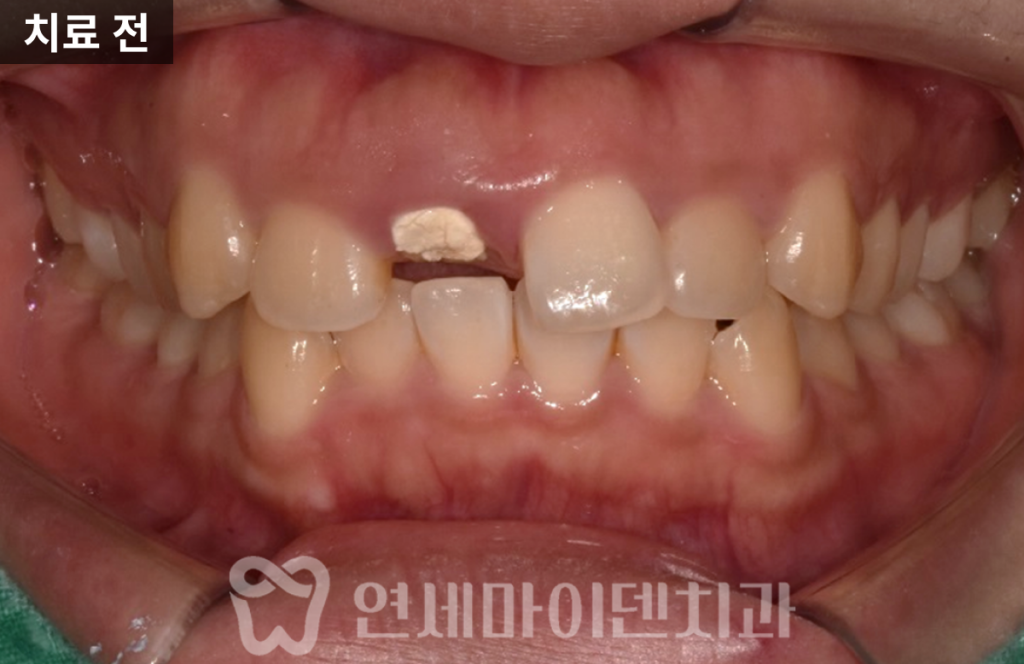

이 환자분 역시 “앞니가 잇몸 근처까지 부러졌다”는

주소로 내원하셨습니다.

기존 치과에서는 발치를 권유받았고,

임플란트를 피하고 싶어 3주 동안 치아 없이 지내며

고민하시다가 저희 병원을 찾아오신 케이스였습니다.

내원 당시 치아는 잇몸 라인과

거의 동일한 위치에서 깨져 있었습니다.

치아가 사라진 자리는 잇몸이 차올라 있고,

잇몸 레벨도 양쪽과 다르게 틀어져 있었습니다.